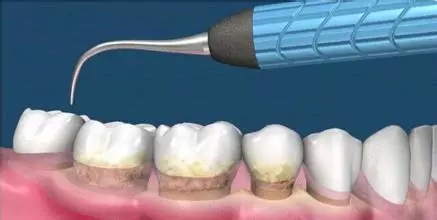

這是牙周病常規(guī)的治療方法,清除或控制臨床炎癥和致病因素,去除病因,消除炎癥。包括口腔衛(wèi)生宣教、充填齲洞、口腔潔治刮治、牙體牙髓治療、咬合調(diào)整、去除不良修復(fù)體、藥物治療(輔助手段,局部用藥效果好)、拔除治療效果不佳的牙周病患牙等。

牙周炎發(fā)展到一定階段時(shí),僅采用基礎(chǔ)治療難以取得較好療效,必須通過(guò)適時(shí)而合宜的手術(shù)治療挽救患牙,才能保持牙周組織健康,延長(zhǎng)患牙在口腔內(nèi)的壽命,維持牙列的完整性,促進(jìn)全身健康。其手段包括齦下刮治、根面平整、牙周翻瓣術(shù)、牙齦切除術(shù)、牙周夾板固定術(shù)等。